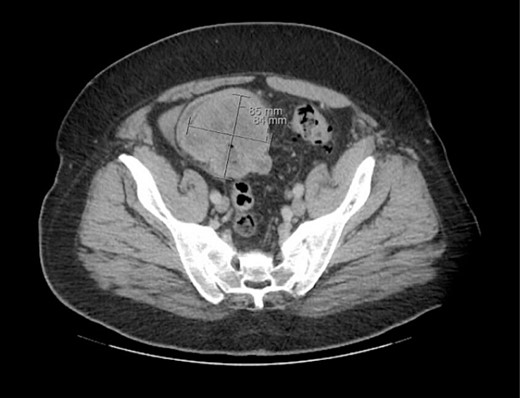

The patient was initially managed nonoperatively with conservative measures including nasogastric (NG) tube decompression, pain control, and serial abdominal exams. Surgery was consulted once CT imaging was obtained (Figs 1–3) and recommended that the patient undergo surgery to resect the identified mass and relieve the obstruction. During the surgical exploration, a mass originating from the terminal ilium was identified that was densely adhered to the peritoneum, bladder, and sigmoid colon, requiring careful dissection. The mass, three lymph nodes, and 29 cm of associated small bowel segment was resected with grossly negative margins, with the mass measuring 7 cm × 8 cm × 9.5 cm. A side-to-side anastomosis was created and the specimens were sent to pathology for further investigation. Postoperatively the patient was hospitalized for 7 days for pain control and monitoring. On postoperative day eight he was discharged with follow up appointments with oncology, general surgery, and a referral to an academic cancer center.

Initial CT imaging, coronal cut, showing necrotic mass causing small bowel obstruction.